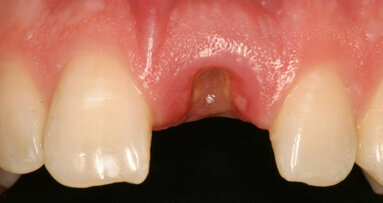

Recent periapical radiographs showed internal resorption in the upper incisors (Fig. 5). The patient sustained additional trauma to the maxillary right central incisor through a fall, which resulted in complete fracture of the crown (Fig. 6). The tooth was nonrestorable.

After reviewing the different treatment options, the patient decided on an immediate implant restoration. Although the maxillary left central incisor also exhibited signs of internal resorption, it was decided that treatment of that tooth would be performed at a later date.